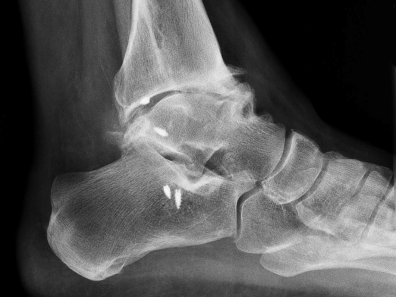

Arthrose des Sprunggelenks

Die OSG-Arthrose bezeichnet den Verschleiss des Gelenkknorpels des oberen Sprunggelenks (OSG), d.h. es handelt sich um eine degenerative Gelenkerkrankung.

Die Ursachen für eine OSG-Arthrose können vielfältig sein. Häufiger als bei anderen Gelenken handelt es sich jedoch um eine posttraumatische Veränderung. Das heisst eine Gelenkabnutzung, die durch einen Unfall mit Knochenbruch oder schwererer Weichteilverletzung einhergeht.